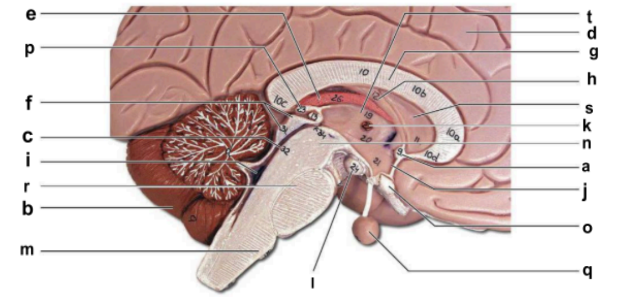

Identify the structure labeled “a” in the image.

anterior commissure

Identify the structure labeled “b” in the image.

cerebellum

Identify the structure labeled “c” in the image.

cerebral aqueduct

Identify the structure labeled “d” in the image.

cerebral hemisphere

Identify the structure labeled “e” in the image.

choroid plexus

Identify the structure labeled “f” in the image.

corpora quadrigemina

Identify the structure labeled “g” in the image.

corpos callosum

Identify the structure labeled “h” in the image.

fornix

Identify the structure labeled “i” in the image.

fourth ventricle

Identify the structure labeled “j” in the image.

hypothalamus

Identify the structure labeled “k” in the image.

interthalamic adhesion

Identify the structure labeled “l” in the image.

mammilary body

Identify the structure labeled “m” in the image.

medulla oblongata

Identify the structure labeled “n” in the image.

midbrain

Identify the structure labeled “o” in the image.

optic chiasma

Identify the structure labeled “p” in the image.

pineal gland

Identify the structure labeled “q” in the image.

pituitary gland

Identify the structure labeled “r” in the image.

pons

Identify the structure labeled “s” in the image.

septum pellucidum

Identify the structure labeled “t” in the image.

thalamus